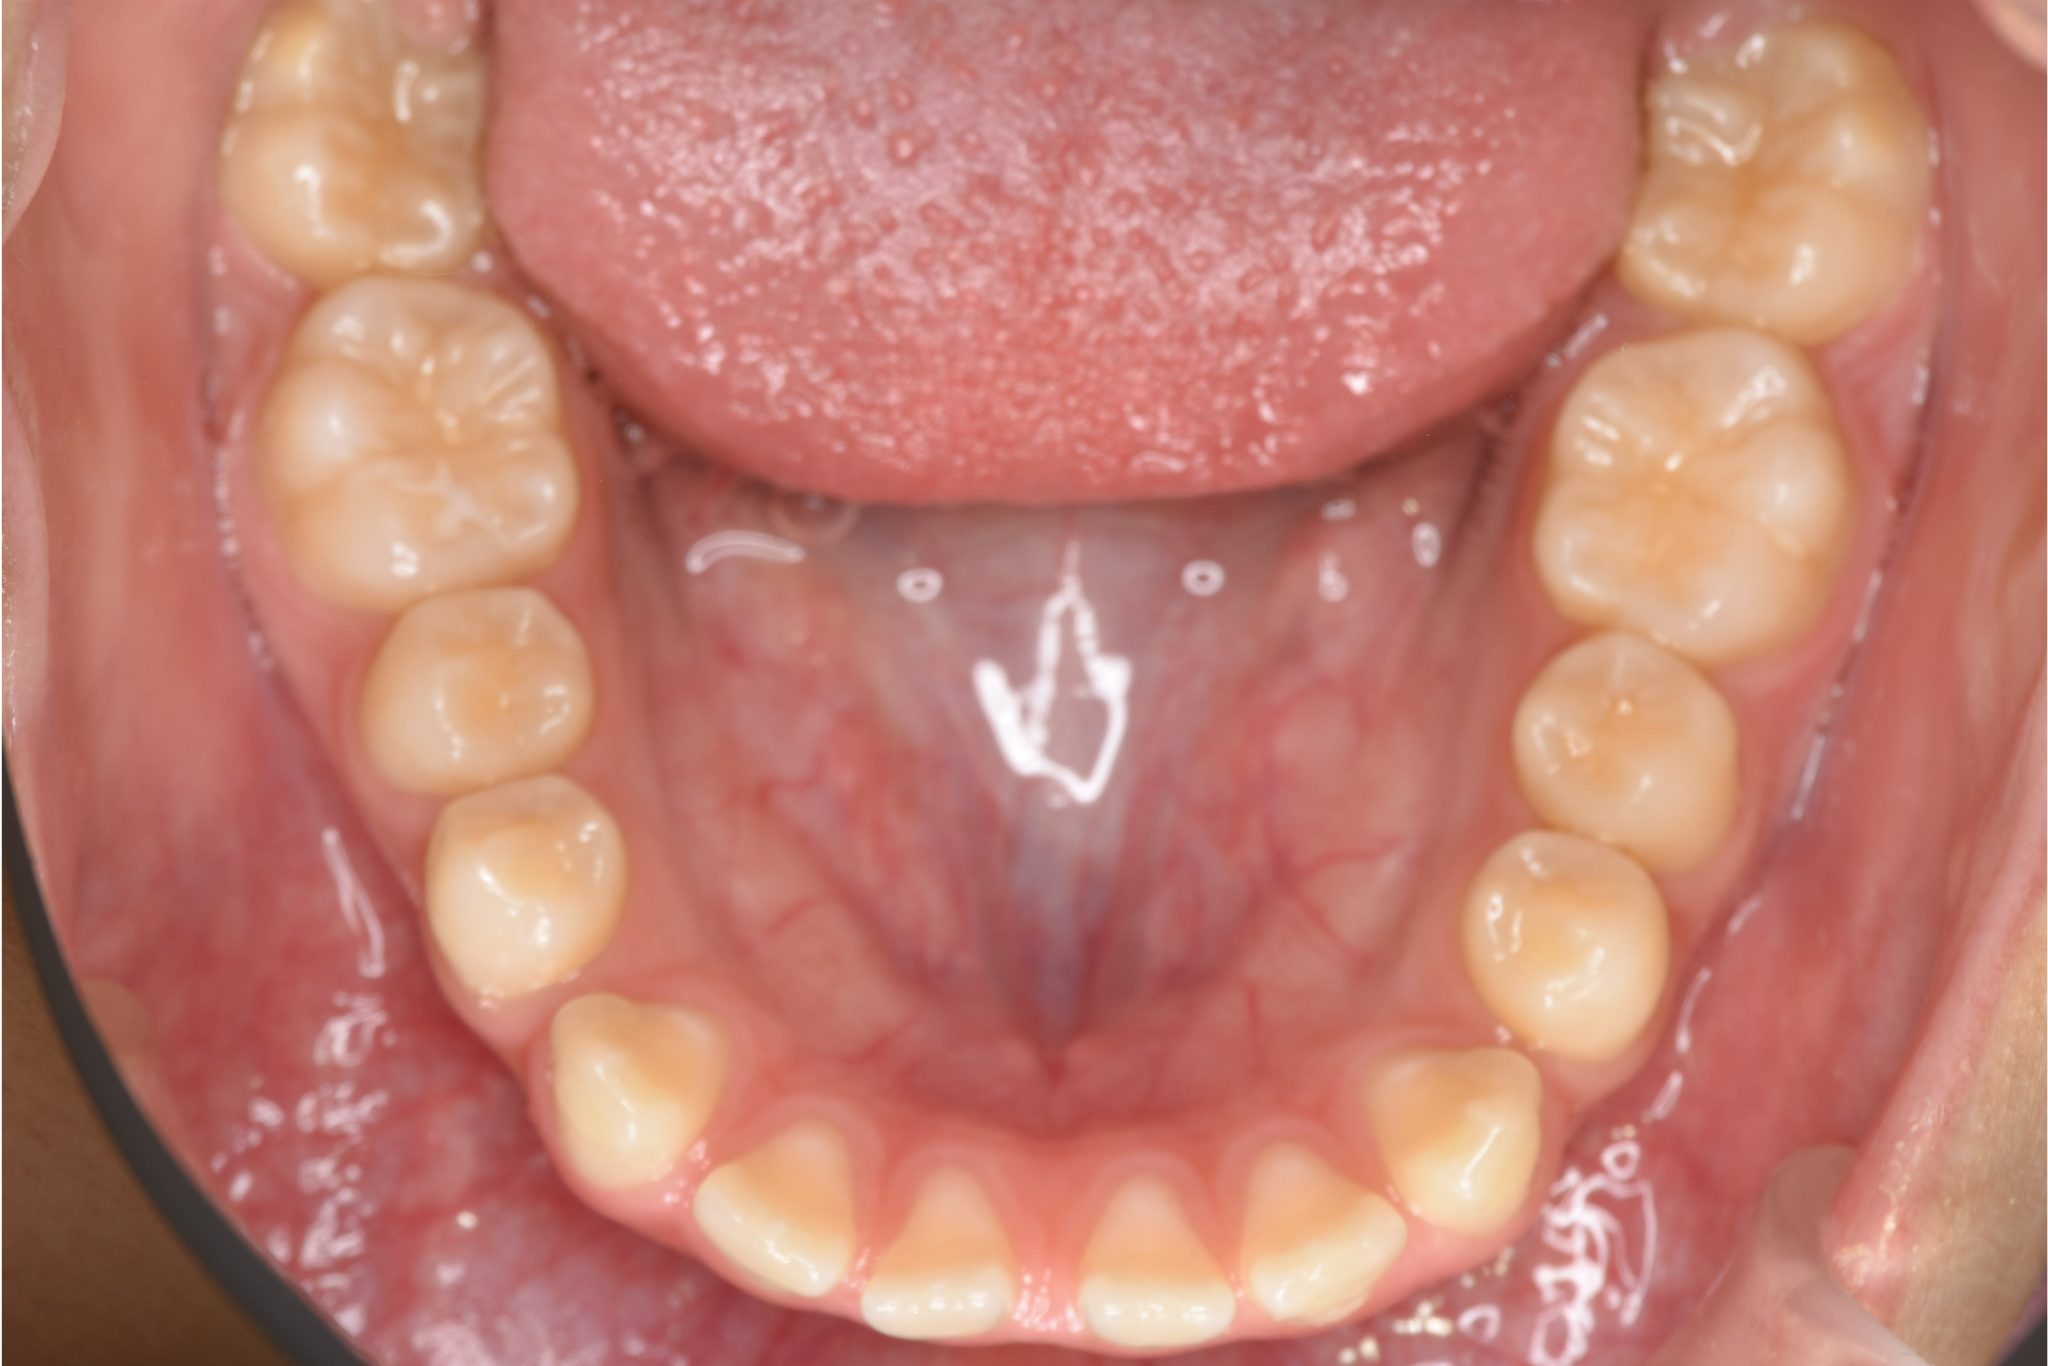

ビフォー

ワイヤー矯正治療|症例_681

主訴 上前歯が出ている|よく口が開いている

施術内容 上顎急速拡大装置と下顎リンガルアーチを用いて上下顎骨を拡大した。

その後マルチブラケット装置を用いて

非抜歯で歯牙を配列し良好な咬合を獲得した。

鼻閉症状は改善した。

治癒期間 2年10か月間